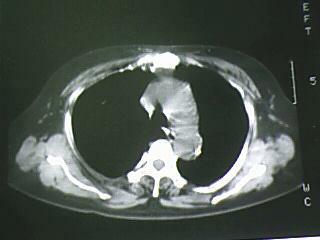

以下是引用bmw011在2009-4-14 19:14:00的发言:[br]右肺继发型肺结核---纵隔淋巴结多发钙化----左肺支扩。支持

以下是引用杀毒软件在2009-4-14 17:52:00的发言:[br]考虑---右肺继发型肺结核---纵隔淋巴结多发钙化----左肺支扩

以下是引用黑白光影在2009-4-14 20:36:00的发言:[br]右肺继发型肺结核;左下慢性支气管炎性病变。